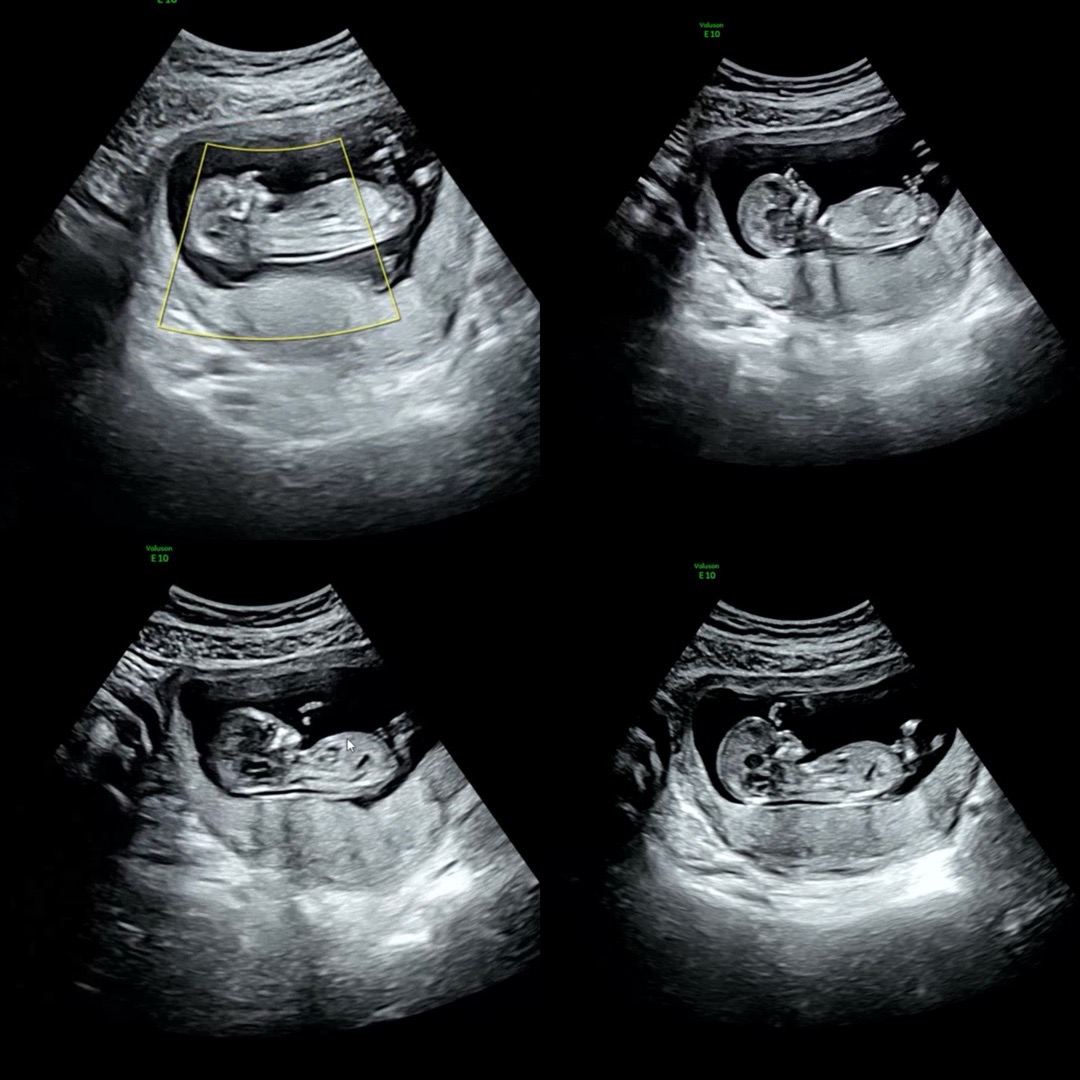

12주5일 각도법 사진 다시 올려봐요!!

각도법으로 알 수 없는 사진이라고 하셔서 다시 다양하게 올려봐요…!ㅎㅎ 저는 아직도 봐도 모르겠네요 ㅠㅠ